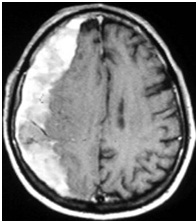

Computed tomography (CT) is the traditional approach utilized to diagnose traumatic brain injury (TBI). Its use has been highest in community hospitals and among practitioners without pediatric training. Interest has increased regarding alternate imaging modalities with the growing concern regarding radiation dosage for pediatric patients . The limited availability of magnetic resonance imaging (MRI) and the time and sedation required deter widespread adoption [21]. Standard MRI has been shown in retrospective comparison as a more sensitive diagnostic tool for intraparenchymal lesions [22]. When rapid MRI is compared to CT there is excellent correlation in the identification of extra-axial hemorrhage, contusion, intraparenchymal hemorrhage, skull fracture and diffuse axonal injury [23].